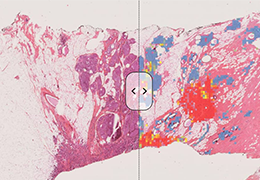

ART-Plan™ Artificial Intelligence Contouring